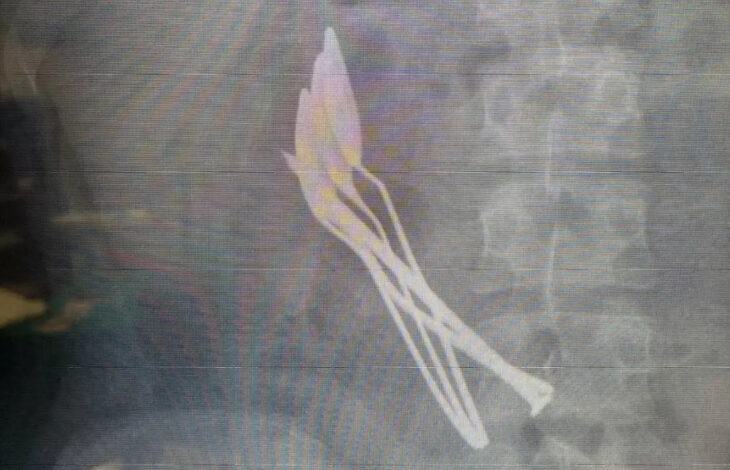

Son olarak ailesi tarafından hastaneye getirilen bir hastanın midesinden ameliyatla 4 metal kaşık ve 1 demir çivi çıkaran uzman hekimler, özellikle zihinsel engelli çocuğu olan aileleri, ölüme kadar götürebilecek yabancı cisim yutma vakalarına karşı çok daha dikkatli olmaları konusunda uyardı.